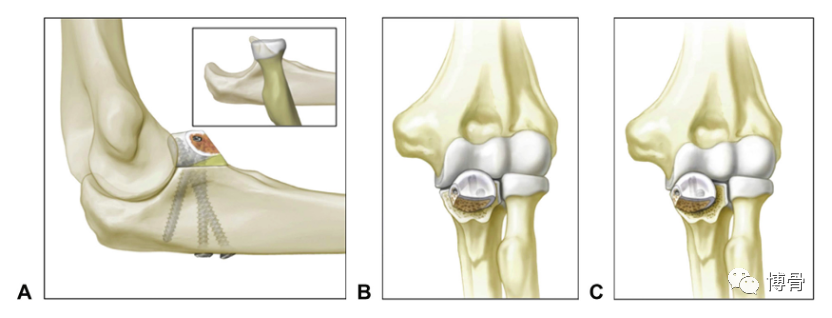

1. 3. 骨软骨移植(osteochondral graft techniques)

骨软骨移植物重建冠状突,可选用自体桡骨头、尺骨鹰嘴尖、肋骨等,同种异体桡骨头也常用于此技术。

桡骨头重建尺骨冠状突,三枚螺钉固定

鹰嘴尖重建冠状突

冠状突假体置换